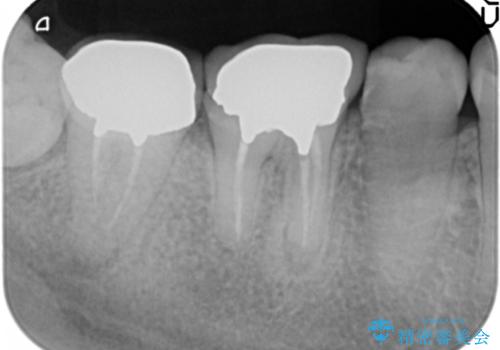

治療途中で長期間放置していたため、歯が歯ぐきから挺出(伸びてくる)してしまい、十分に強度を担保できるセラミッククラウンを装着するスペースが不足した状態です。

加えて、舌の邪魔になっている骨隆起や根尖病変といった問題を歯周外科・精密根管治療を行い、しっかりとスペースを確保したのちセラミッククラウンを作製していきます。